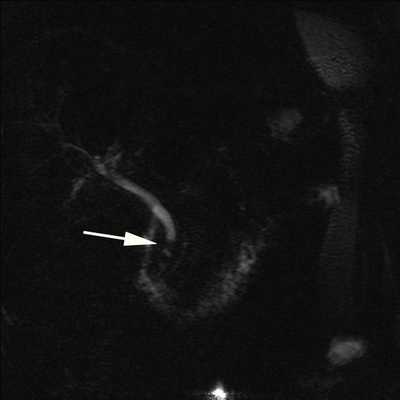

Изображение 4. 55-летний мужчина после удара бейсбольной битой по животу. На МСКТ-снимке (А) обнаружена большая рваная рана головки поджелудочной железы (стрелка), затрагивающая более 50 % толщины паренхимы и указывающая на высокую вероятность повреждения протока.

На магнитно-резонансной холангиопанкреатографии (В) у того же пациента подтверждается повреждение протока (стрелка).

Изображение 5. Разрыв поджелудочной железы IV степени у 41-летнего мужчины, пострадавшего в результате ДТП. На МСКТ (А) показан линейный разрыв (стрелка) в головке поджелудочной железы справа от верхней брыжеечной вены.

На МРТ (В) изображение того же пациента демонстрирует разрыв в головке поджелудочной железы (стрелка).